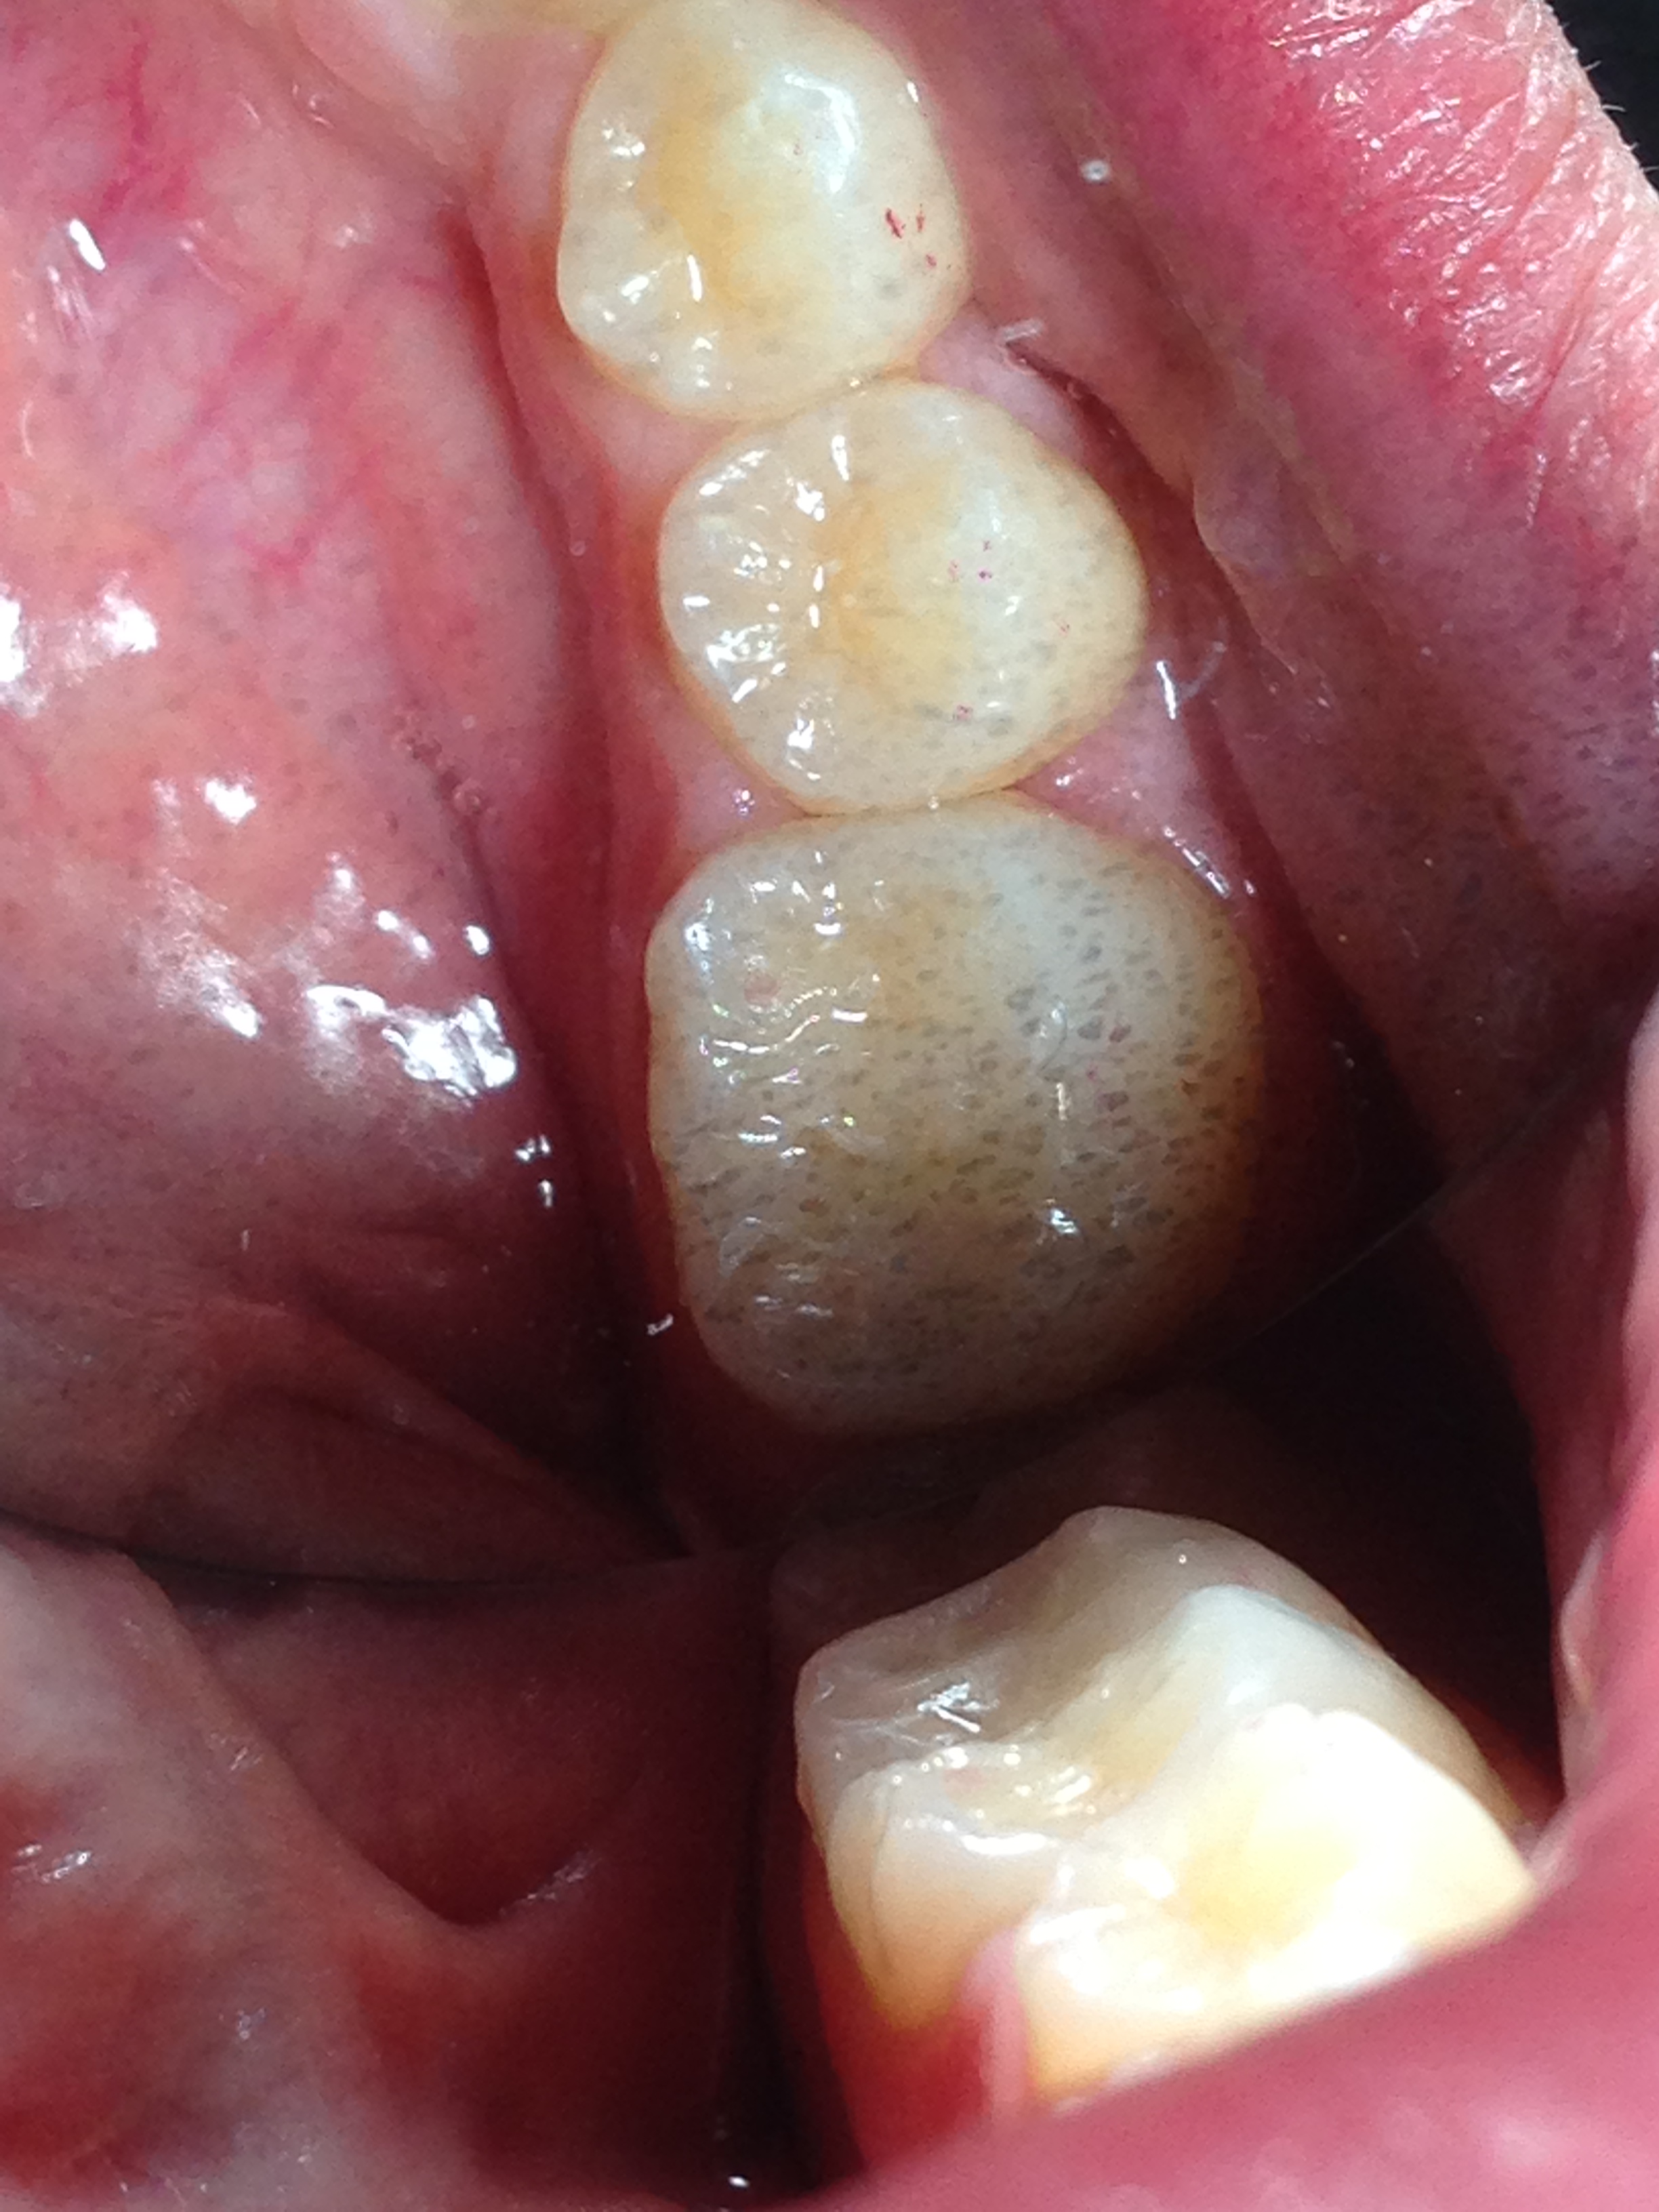

L'odontoiatria conservativa è un particolare ramo che tratta il restauro e la cura di tessuti cariati o danneggiati irreparabilmente.

Il procedimento classico è quello della semplice chiusura del foro nel caso in cui si tratti di una carie o, in presenza di un elemento scheggiato si agisce ricreando nei minimi dettagli l'originale anatomia del dente. In entrambe le situazioni si usa il composito, materiale che ha come fiore all'occhiello la minima invasività grazie alla sua forte adesione ai tessuti dentali; inoltre il colore e la resistenza alla masticazione renderanno il dente curato indistinguibile da uno sano.